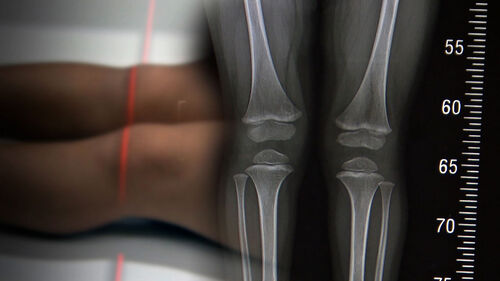

Q. 예상 키는 아이 성장판을 엑스레이 찍고 그렇게 해서 예상을 한다는 건데, 그래도 대략 맞나 보죠?

아빠 키와 엄마 키를 더해서 하는 거는 정말 추정치인 거고, 만약에 그게 맞다면 사실은 형제자매가 다 키가 똑같아야 되는데 그렇지 않잖아요. 이거는 사실은 경향을 보는 것뿐이고, 성장판을 찍는 거는 요새 높게 보고하는 데는 95%까지 보고합니다. 꽤 정확해요.